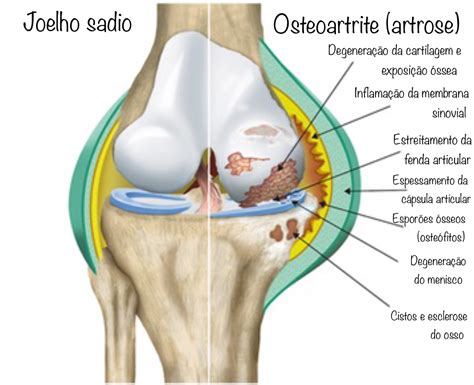

Entre as principais alterações que a artrose causa no joelho estão:

- Desgaste da cartilagem articular: reduz a proteção entre os ossos e causa atrito.

- Inflamação crônica da articulação: leva a dor e inchaço frequentes.

- Formação de osteófitos (bicos ósseos): pequenas projeções que surgem nas bordas dos ossos.

- Rigidez articular: dificuldade para dobrar ou estender completamente o joelho.

- Perda da função: limitações para caminhar, agachar ou realizar atividades simples.

Com o avanço do desgaste, o joelho perde seu alinhamento natural e pode se desviar para dentro (joelho em “X”) ou para fora (joelho em “O”).

Essas deformidades aumentam ainda mais a sobrecarga na articulação, acelerando o processo degenerativo.